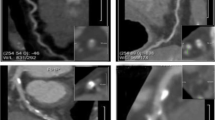

The best diastolic and systolic reconstruction images were imported into the postprocessing workstation (syngo.via, Somatom Force, Siemens Healthineers), and coronary artery stenosis and CACs were analyzed by two experts with more than 10 years of experience in cardiovascular disease diagnosis. Obstructive CAD was defined as coronary CTA showing maximum diameter stenosis of ≥ 50% including groups III and IV. The disease groups were divided into 0 Agatston units (AU), 1–99 AU, 100–299 AU, and ≥ 300 AU according to the CACs. The commercial software (Medis suite version 3.0, Leiden, The Netherlands) automatically calculated the following cardiac functional parameters using data of 20 phases per cardiac cycle: LV end-diastolic volume (LVEDV), LV end-systolic volume (LVESV), stroke volume (SV), cardiac output (CO), LV ejection fraction (LVEF), global radial strain (GRS), circumferential strain (GCS), longitudinal strain (GLS). LV radial and circumferential strains were quantified on the short axis, whereas LV longitudinal strains were quantified on the long axis including 2-chambers, 3-chambers, 4-chambers and then averaged (Fig. 1).

The differences in LV global myocardial strain between the two groups are shown in Fig. 3. The GRS, |GCS|, and |GLS| in the obstructive CAD group were significantly smaller than those in the non-obstructive CAD group. An example for LV myocardial strains based on CT in patient with CAD was shown in Fig. 4.

A 28-year-old man admitted with angina pectoris, CAD-RADS 5. (a) Image showed coronary artery calcification score of 0; (b) MPR revealed the anterior descending branch lumen obstruction (arrow); (c) curves of myocardial strain and time in the cardiac cycle. The peak systolic strains of the left ventricular myocardium were markedly decreased. Red, blue, green represents myocardial global radial strain, global longitudinal strain, and global circumferential strain respectively.